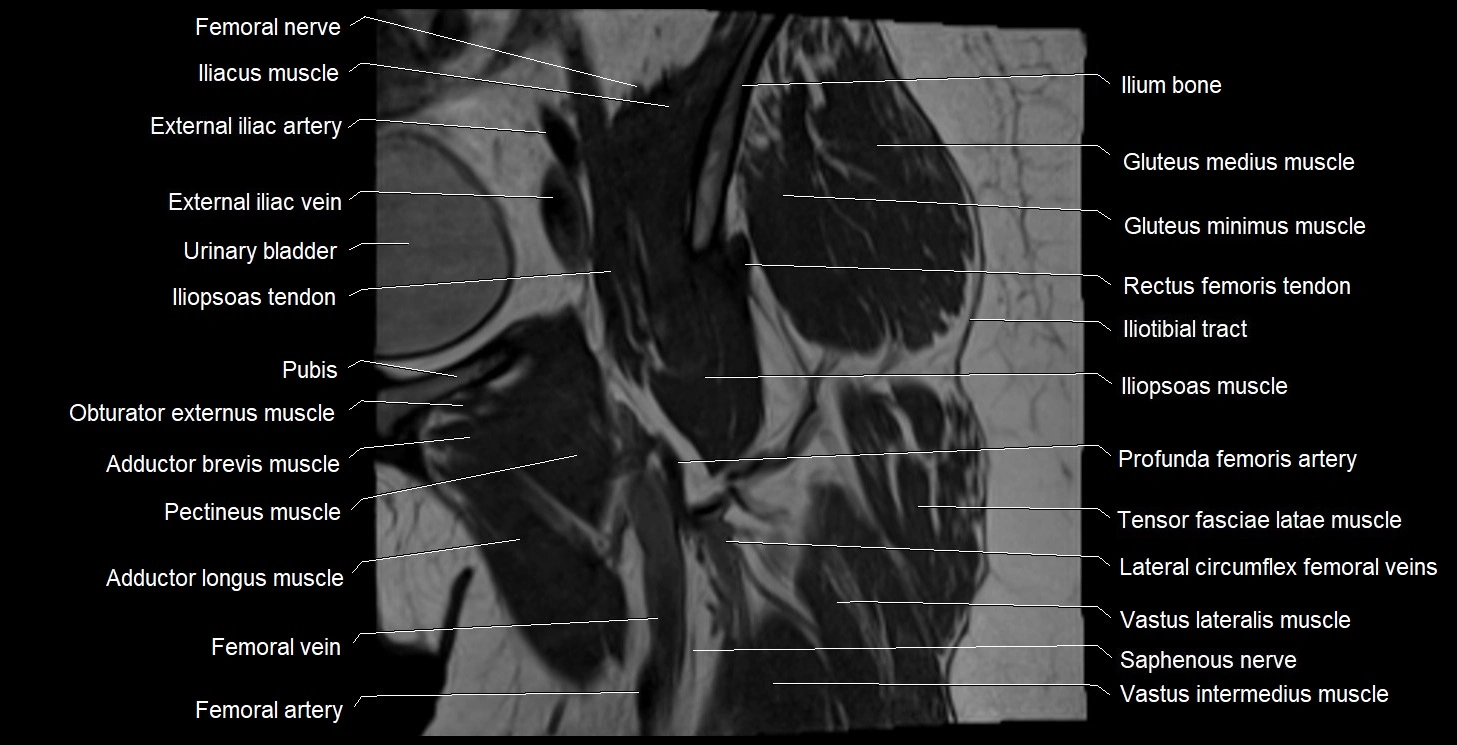

- Adductor brevis muscle

- Adductor longus muscle

- External iliac artery

- External iliac vein

- Femoral artery

- Femoral nerve

- Femoral vein

- Femur

- Gluteus medius muscle

- Gluteus minimus muscle

- Gracilis muscle

- Iliopsoas muscle

- Iliopsoas tendon

- Iliotibial tract

- Ilium bone

- Lateral circumflex femoral veins

- Pectineus muscle

- Saphenous nerve

- Tensor fasciae latae muscle

- Vastus intermedius muscle

- Vastus lateralis muscle